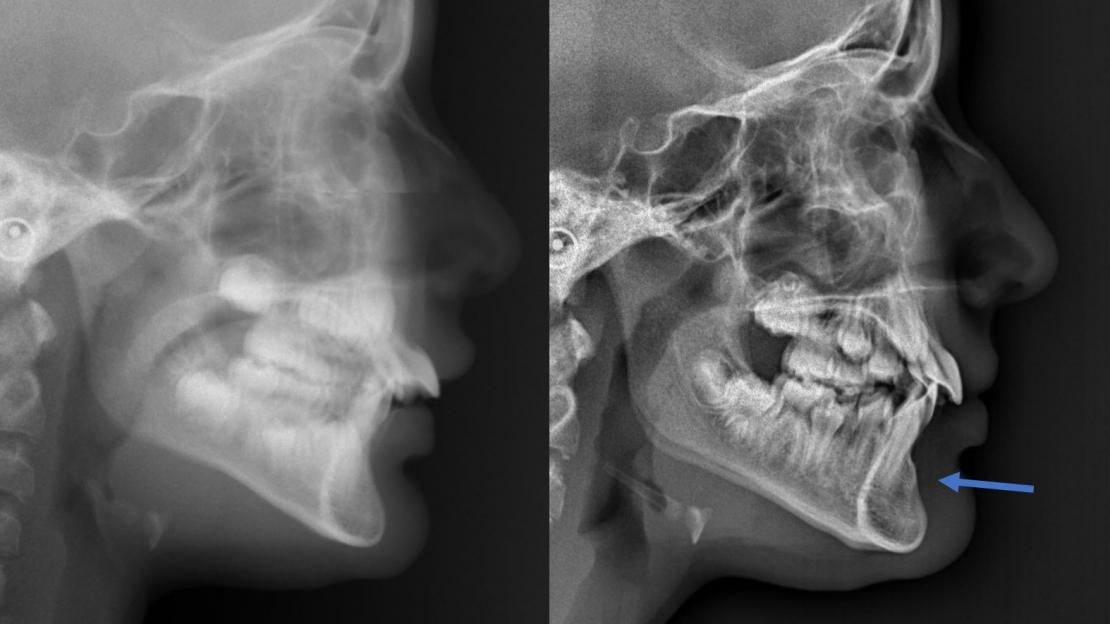

- Finesse, fenestration voire absence d’os en vestibulaire des incisives (sur téléradiographie de profil ou CBCT)

Cette technique permet à court terme d’aboutir à une muqueuse cicatricielle fixée au périoste et ainsi d’augmenter la hauteur de la gencive attachée. Une hauteur de gencive attachée suffisante permet de prévenir les récessions et une inflammation de la marge gingivale en cas de difficultés à l’hygiène buccale. A moyen terme, nous observons aussi une apposition osseuse alvéolaire vestibulaire sur les téléradiographies de profil avec une avancée du point B. Il y a donc amélioration de la résistance parodontale Rp au niveau gingival et au niveau alvéolaire.

Pratiquée en interception, en début de traitement ou en cours de traitement orthodontique, cette technique permet grâce à la diminution des contraintes musculaires centripètes un repositionnement antérieur spontané de la racine des incisives dans la symphyse. Les proalvéolies mandibulaires se corrigent d’environ 10° en 6 à 12 mois. Nous observons aussi une libération de la croissance mandibulaire avec un début de correction spontanée des rétromandibulies.